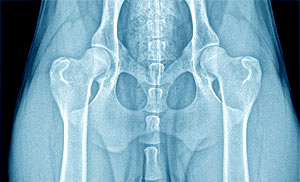

3 D – stredný

zreteľná anatomická nepravidelnosť, zrejmá inkongruencia kĺbových plôch hlavice femuru a acetabula, artróza, stred hlavice leží laterálne od DOA

100° - 90°

4 E - ťažký

výrazná anatomická nepravidelnosť, výrazná subluxácia až

luxácia hlavice femuru z acetabula, ťažká artróza, deformity krčku, hlavice i acetabula

Menej ako 90°